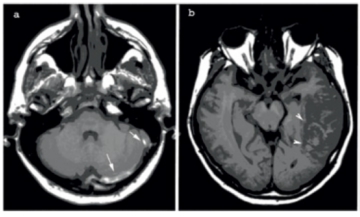

• stadiul II (subacut între ziua a 6-a şi a-15 zi: metHb intracelulară) – trombul apare în hipersemnal atât T1, DP cât şi în ponderaţie T2 (Fig.1)

• Stadiul III – infarct venos propriu-zis = zona mixtă, cu edem si hemoragie (vezi Fig.1), cortico-subcorticală, secundar rupturii venelor corticale.